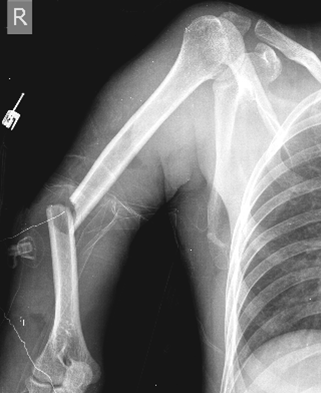

HUMERUS KIRIKLARI

Doktor Mehmet Subaşı

Humerus kemiği omuz ile dirsek arasında yer alan kol bölgesinin kem...

HUMERUS BOYUN KIRIKLARI

Humerus üst uç kırıkları içinde değerlendirilmekte ol...